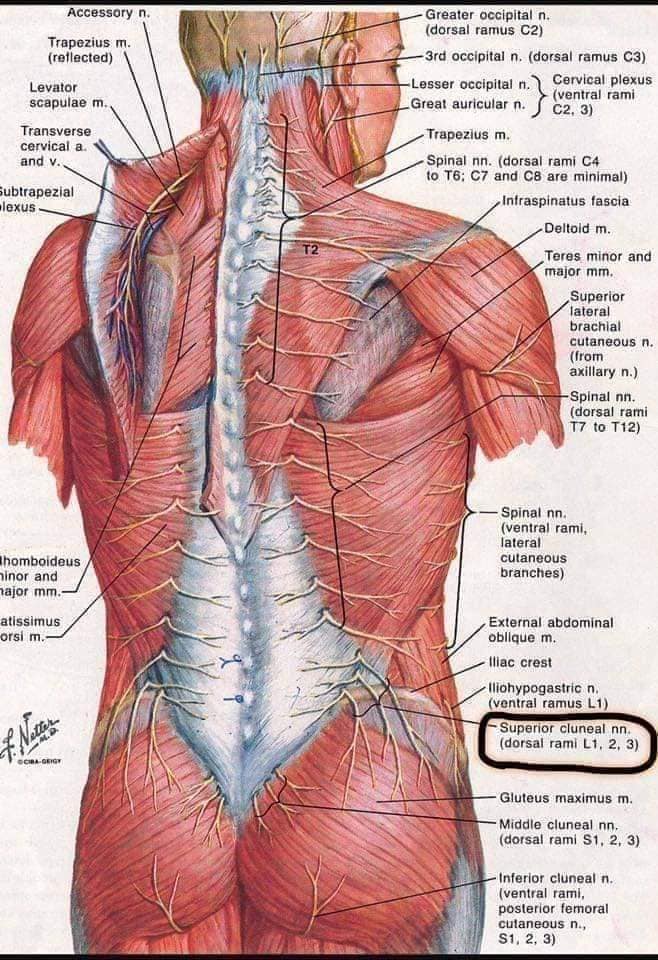

Спинні м'язи

Спинні м'язи виконують функції підтримки хребта, а також дозволяють здійснювати рухи тулуба.

Поверхневі спинні м'язи

М'язи, що піднімають лопатку: Трапецієподібний м'яз: великий м'яз, що покриває верхню частину спини. Його функція - підтримка і рух лопаток, а також забезпечення стабільності хребта.

М'язи, що ведуть лопатку до хребта: Широкий м'яз спини: великий м'яз, що розташований в нижній частині спини. Він відповідає за рухи плечей і лопаток, а також за розширення верхньої частини тулуба.

Глибинні спинні м'язи

М'язи, що забезпечують стабільність хребта: М'язи, що розташовані між хребцями: включають мускулатуру, яка забезпечує стабільність і підтримку хребта, а також дозволяє здійснювати рухи хребта.

М'язи, що здійснюють ротацію та нахили

М'язи, що забезпечують ротацію хребта: Ротаційні м'язи: допомагають у здійсненні обертальних рухів тулуба, а також у підтримці рівноваги і стабільності хребта.